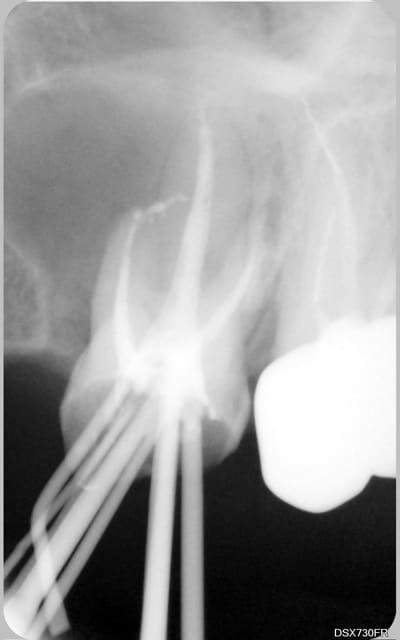

Bel exemple du genre d'endo que je reprends au quotidien juste à coté de ta 7, lentulo fracturé et autres cochonneries.

et les instruments dans la 6, c'est toi? ;)

non, je déconne, je déconne.

joli résultat quand même.

"Qui n'a jamais cassé une lime endo lui jette le premier cône de gutta ! "